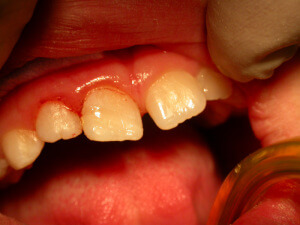

Dental Trauma

Various injuries at the face or the teeth are a serious and urgent situation that needs different kind of treatment approach analogous to the kind of trauma. Quite often, a tooth is broken, a tooth next to the previous has been moved towards the palate or the lips and another one has suffered concussion or extrusion. Specialized and immediate care is needed for the teeth to be saved.

The prevention is focused on the application of an athletic mouthguard of protection, especially if the child takes part in a sport. Besides contact sports like tae kwon do, mouthguards are useful for cycling, basketball, football, skiing, skating etc.